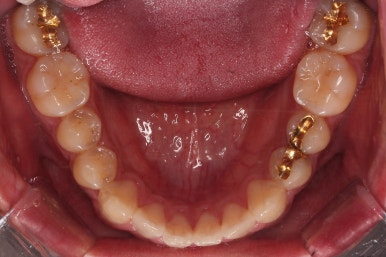

초진 시 입안의 모습입니다.

비교적 고른 편이긴 하나 아랫니가 전반적으로 밀려 나오면서 앞니끼리 부딪혀 있는 양상이고요.

어금니 맞물림도 긴밀하게 톱니바퀴처럼 위아래가 맞물려 있는게 아니라 엉성한 모습이죠.

앵글씨 3급 부정교합이라고 하는데요.